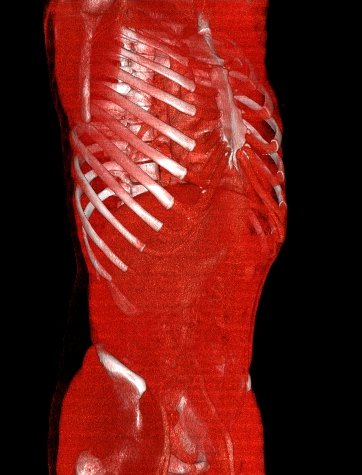

白色文字(排除指定关键词) Imaging Anatomy: interactive PACS-like atlas of radiological anatomy

解剖学模块